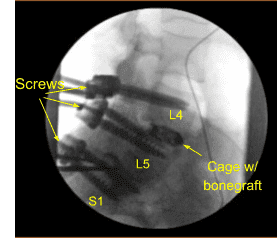

Se colocó un aloinjerto de matriz ósea desmineralizada en el interespacio y luego se colocó un dispositivo intersomal expansible de titanio bajo guía fluoroscópica tras cubrir estérilmente la unidad C-arm. La AP y la imagen lateral mostraron una posición correcta y luego la jaula se amplió hasta el ajuste adecuado, y la radiografía posterior mostró una buena posición tanto en la línea media como en anteroposterior.

A continuación, se obtuvo un nuevo TAC, que mostró la posición correcta de los nuevos tornillos pediculares y del separador intercarrocés. Los procesos transversales bilaterales de L4, L5 y ala lateral fueron decorizados para la artrodesis. Las varillas precortadas y pre-contorneadas se reflejaban y colocaban sobre los tulipanes desde L4 hasta S1, se aseguraban con tapones de bloqueo y finalmente se apretaban con el dispositivo de par y antitorque.